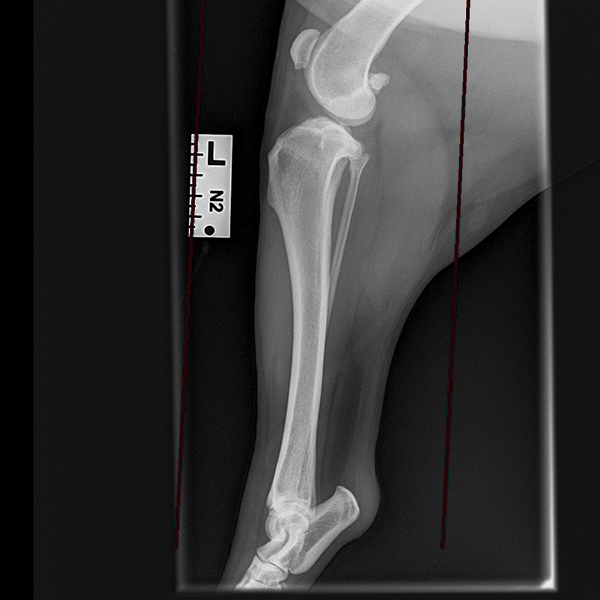

Dogs with cruciate ligament rupture often have a progressive deterioration in the use of their leg over many months. Initially, lameness is mild and transient and tends to rapidly improve with rest and anti-inflammatory medication. This mild and intermittent lameness is typical of the early stages of cruciate ligament rupture when most of the ligament is still intact and functioning. If untreated at this stage, the ligament will progressively tear, and lameness will become persistent and severe; this corresponds to a complete rupture of the ligament. TPLO surgery is the treatment of choice at any stage of cruciate ligament rupture. We recommend early treatment since this can prevent full ligament rupture from occurring, thereby hastening your pet’s recovery and improving their comfort and mobility. Drag the circle to view before and after surgery images.

TPLO surgery changes the way that the two knee bones (femur and tibia) interact through cutting, repositioning and fixing the tibia in a slightly different position. This provides joint stability without the need to replace the cruciate ligament.